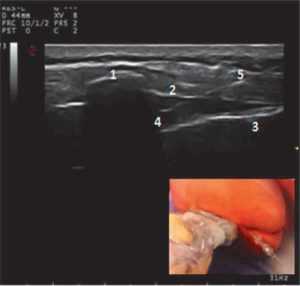

В группу КА вошли 23 ребенка, у которых в качестве компонента сочетанной анестезии проводили каудальную эпидуральную блокаду, которая выполнялась за 15 мин до разреза. Пациентам группы КА в условиях общей анестезии и ИВЛ (севофлураном 1 МАК) проводили ультразвуковое (УЗ) исследование в латеральной или prone-позиции (у детей старшего возраста) высокочастотным линейным датчиком. Определяли каудально-эпидуральное пространство методом “out of plane” по короткой оси (рис. 1). У детей старшего возраста идентификация каудально-эпидурального пространства проводилась конвексным датчиком. После ротации ультразвукового датчика на 90 градусов между крестцово-копчиковой связкой, крестцовыми рогами и крестцом находили гиперэхогенное пространство — каудально-эпидуральное пространство. Иглу для блокады (30 мм 25G) вводили в плоскости луча сканирования и визуализировали в гиперэхогенном пространстве под очертанием крестцового рога.

Рис. 1. Ультразвуковое изображение каудально-эпидурального пространства (сагиттальный скан):

1 — крестцовые рога; 2 — крестцово-копчиковая связка (мембрана); 3 — копчик; 4 — каудально-эпидуральное пространство; 5 — игла в проекции сканирования

Fig. 1. Ultrasound image of the caudal-epidural space (sagittal scan)

1 — sacral horns; 2 — sacrococcygeal ligament (membrane); 3 — tailbone; 4 — caudal-epidural space; 5 — a needle in a projection of scanning.